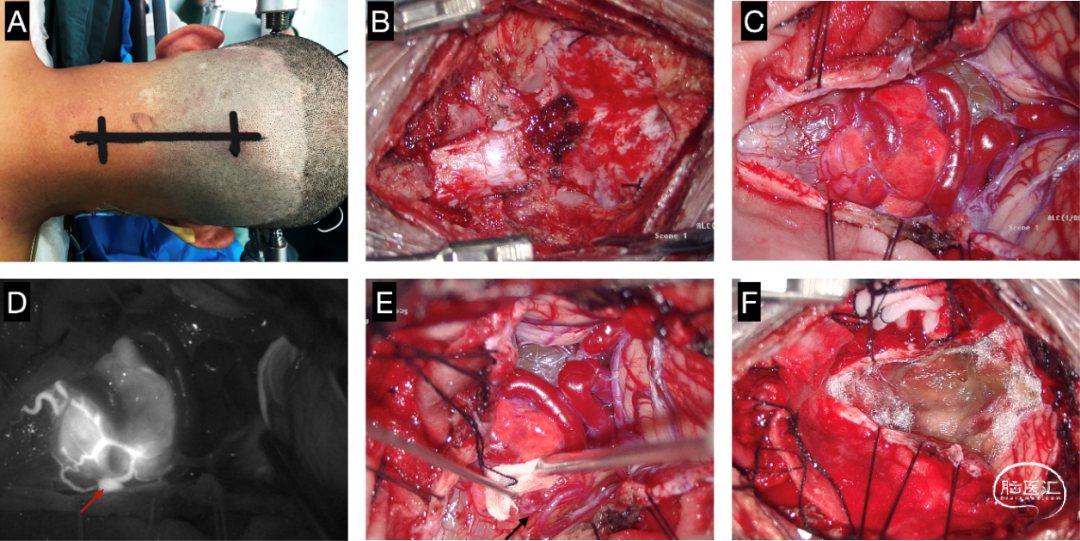

患者气管插管全麻成功后取俯卧位,Mayfield头架固定。取枕下后正中入路(图2 A),常规消毒铺巾。逐层切开皮肤、皮下,经正中白线分离两侧肌肉,撑开器撑开暴露枕骨鳞部、寰椎。磨钻铣刀开颅,打开寰椎后弓(图2 B)。“Y”形剪开硬脑膜,暴露双侧小脑扁桃体及上颈髓背部,见肿瘤位于延髓背侧,呈粉红色,边界清,质地软,血供丰富,肿瘤背侧可见粗大引流静脉(图2 C)。静脉快速注射吲哚菁绿(ICG)12.5mg,显微镜荧光模式下辨别可疑的供血动脉(图2 D-E),采用临时夹阻断可疑供血动脉,再次ICG造影,肿瘤显影明显延迟,提示阻断血管为主要供血动脉。电凝并切断主要供血动脉,沿肿瘤与延髓边界分离,将其完整切除,最后电凝切断引流静脉(图2 F)。术中持续监测体感、运动诱发电位未见明显异常。手术区域反复冲洗,无活动性出血,速即纱贴敷创面,人工脑膜缝合修补硬膜缺损,回纳骨瓣,钛链+钛钉固定。逐层关颅,术毕。术后标本送常规病理。

图2. 延髓血管母细胞瘤手术过程。(A)取后正中直切口,(B)打开枕骨大孔及寰椎、枢椎后弓,(C)Y形剪开硬脑膜,打开蛛网膜后完整暴露肿瘤,(D)术中ICG造影确认主要供血动脉,(E)首先电凝切断供血动脉,然后将肿瘤完整切除(F)。